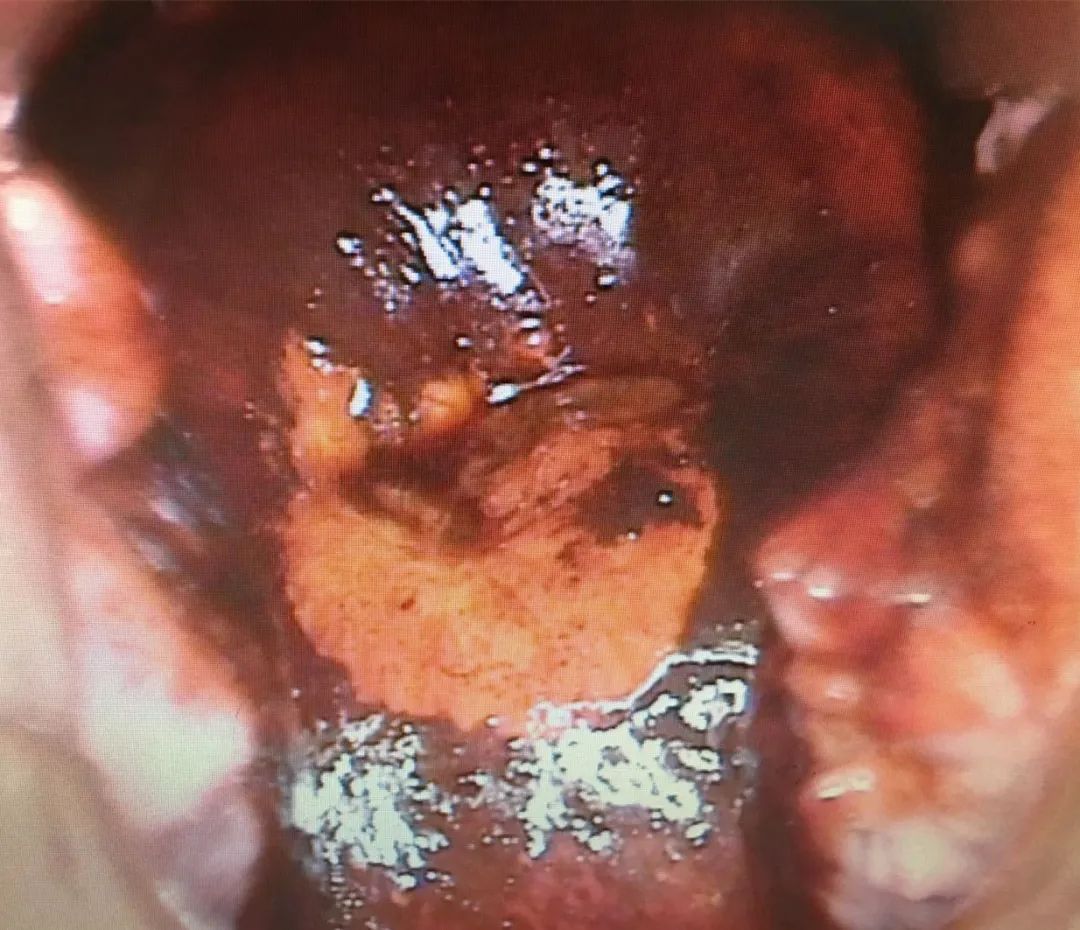

当我用阴道镜仔细观察她的宫颈时,发现情况非常糟糕,以我的经验,她这种情况应该是癌前病变的CIN二级。

宫颈CIN,指的是宫颈上皮内瘤变,一共分为三级。一级症状最轻,达到二级,说明已经有可能是癌前病变的现象,这种情况虽然并不是很严重,但是如果不经过治疗,就有可能会达到三级,也可能会出现恶变的现象,有很大概率会发展成宫颈癌,需要尽快做手术处理。

CIN1级

CIN2级 (黑色为涂了复方碘的部位)

CIN3级(黑色为涂了复方碘的部位)